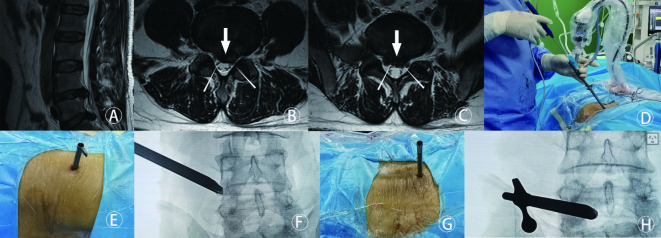

这是一项回顾性研究。本研究探讨经椎间孔入路联合椎间入路(PELD)的经皮内镜下腰椎间盘切除术治疗L4/5和L5/S1两节段椎间盘突出的效果是否不亚于后路腰椎椎间融合术(PLIF)。在这项回顾性研究中,我们纳入了40例L4/5和L5/S1两节段腰椎间盘突出症(LDH)患者,他们接受了PELD (n = 18)或PLIF (n = 22)。两组分为联合组(PELD)和融合组(PLIF)。联合组L4/5节段椎间盘突出采用椎间路入路,L5/S1节段椎间盘突出采用椎间路入路。术前采用MRI检查神经根及硬脑膜受压程度。采用视觉模拟评分(VAS)、Oswestry残疾指数(ODI)、日本骨科协会评分(JOA)和改良MacNab标准评价两组患者术前1周、3个月、6个月、12个月、24个月、36个月及术后最终随访的临床结局。两组患者术后不同时间点的VAS、ODI、JOA评分均较术前显著改善(P < 0.05)。综上所述,本研究旨在比较PELD和PLIF治疗L4/5和L5/S1双节段腰椎间盘突出症的疗效。与PLIF相比,PELD具有术中出血少、手术时间短、无需全身麻醉等优点。然而,PLIF术后复发的可能性较低。总之,两种方法都能给患者带来满意的效果。临床上,外科医生应仔细权衡两种手术的利弊,选择适合患者的手术方式。同时,在今后的研究中,我们应进一步延长随访时间,观察椎体融合术在预防术后复发方面是否更有优势。

This was a retrospective study. The present study investigates whether Percutaneous Endoscopic Lumbar Discectomy via Transforaminal Approach Combined with Interlaminar Approach(PELD) is no less effective than posterior lumbar interbody fusion(PLIF) in the treatment of L4/5 and L5/S1 two-level disc herniation. In this retrospective study, we included 40 patients with L4/5 and L5/S1 two-level lumbar disc herniation (LDH) who received PELD (n = 18) or PLIF (n = 22). The two groups are divided into a united group(PELD) and a fusion group(PLIF). In the united group, the transforaminal approach was adopted for L4/5 level disc herniation, and the interlaminar approach was adopted for L5/S1 level disc herniation. The degree of nerve root and dural compression determined by MRI was taken preoperatively. The clinical outcomes which preoperative 1 week, 3 months,6 months,12 months, 24 months, 36months and final follow-up after surgery between the two groups were evaluated using the visual analog scale (VAS), the Oswestry disability index (ODI), the Japanese Orthopaedic Association (JOA) and the modified MacNab criteria. In both groups, the VAS, ODI and JOA scores at different timepoints postoperatively were significantly improved compared with those preoperatively (P < 0.05). According to the modified MacNab criteria, the excellent or good outcome rate was 94.44% in the united group and 90.91% in the fusion group. Within 1 week after the operation, there was a significant difference in the improvement of clinical symptoms between the combination group and the fusion group (P < 0.05), and the combination group was better than the fusion group. Additionally, within three months postoperatively, the combination group exhibited significantly better functional improvements compared to the fusion group .With the gradual recovery of patients, there was no significant difference in the improvement of clinical symptoms between the two groups (P > 0.05). To sum up, This study aimed to compare the efficacy of PELD and PLIF in the treatment of dual-segmental lumbar disc herniation of L4/5 and L5/S1. Compared with PLIF, PELD has advantages in less intraoperative bleeding, shorter operation time and non-general anesthesia. However, the possibility of postoperative recurrence of PLIF is lower. In short, both methods can bring satisfactory results to patients. Clinically, surgeons should carefully weigh the advantages and disadvantages of the two operations and choose the operation method suitable for patients. At the same time, in future studies, we should further extend the follow-up time to observe whether vertebral fusion has more advantages in preventing postoperative recurrence.